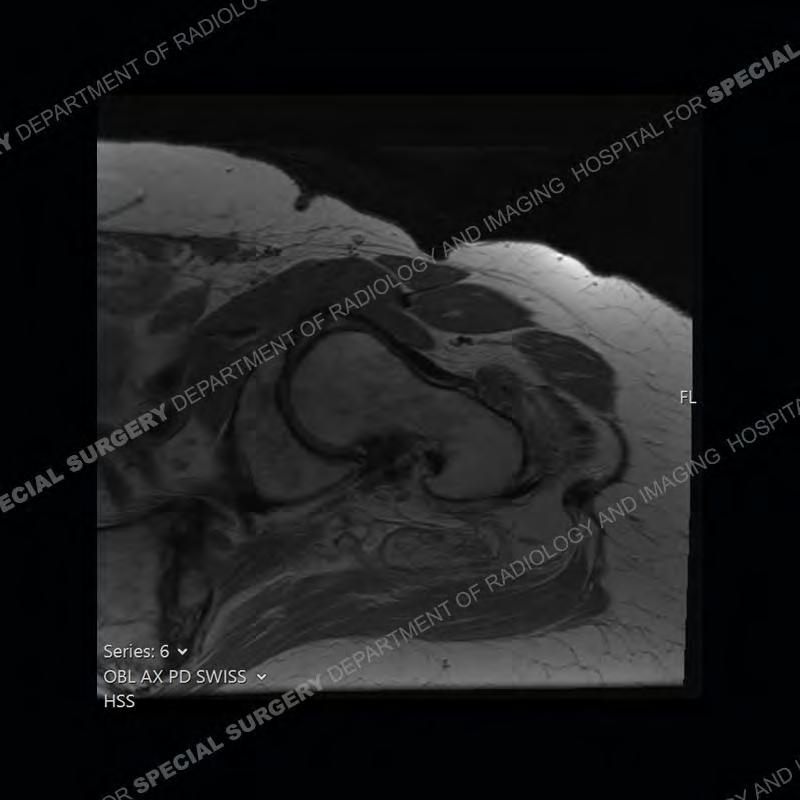

The radiograph is not particularly contributory in this case. The MRI demonstrates markedly abnormal architecture of the gluteus minimus and anterolateral band of the gluteus medius. Portions of the tendons are high signal, portions are highly attenuated, and portions are disrupted. A large, complex fluid collection is present in the adjacent soft tissue.

Diagnosis: Gluteal Tendinosis and Disruption with Complex Trochanteric Bursal Collection

Not as much of a diagnostic dilemma as many of the other cases shown but just a nice example of the pathology seen of the gluteal tendons and a cause of trochanteric pain. Although, frequently thought of in isolation, trochanteric bursitis or bursal thickening is much more commonly a reactive change to underlying pathology of the subjacent gluteal tendons. The gluteus medius is divided into a posterior band and an anterolateral band. Tendinosis and partial tearing very commonly will involve the gluteus minimus and especially the more posterior fibers and then propagate into the anterior lateral band of the gluteus medius. Involvement of the posterior band of the medius is much less common and engenders a marked degree of functional impairment.